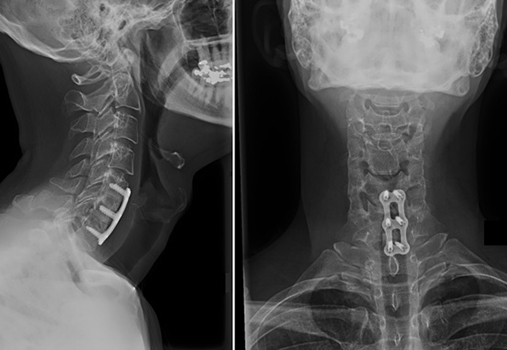

دردهای گردنی

Cervical Pain